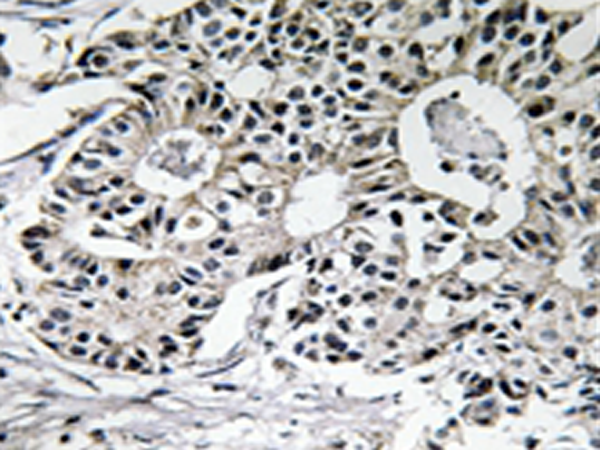

IHC positive control: |

Human breast carcinoma tissue |

IHC Recommend dilution: |

50-100 |